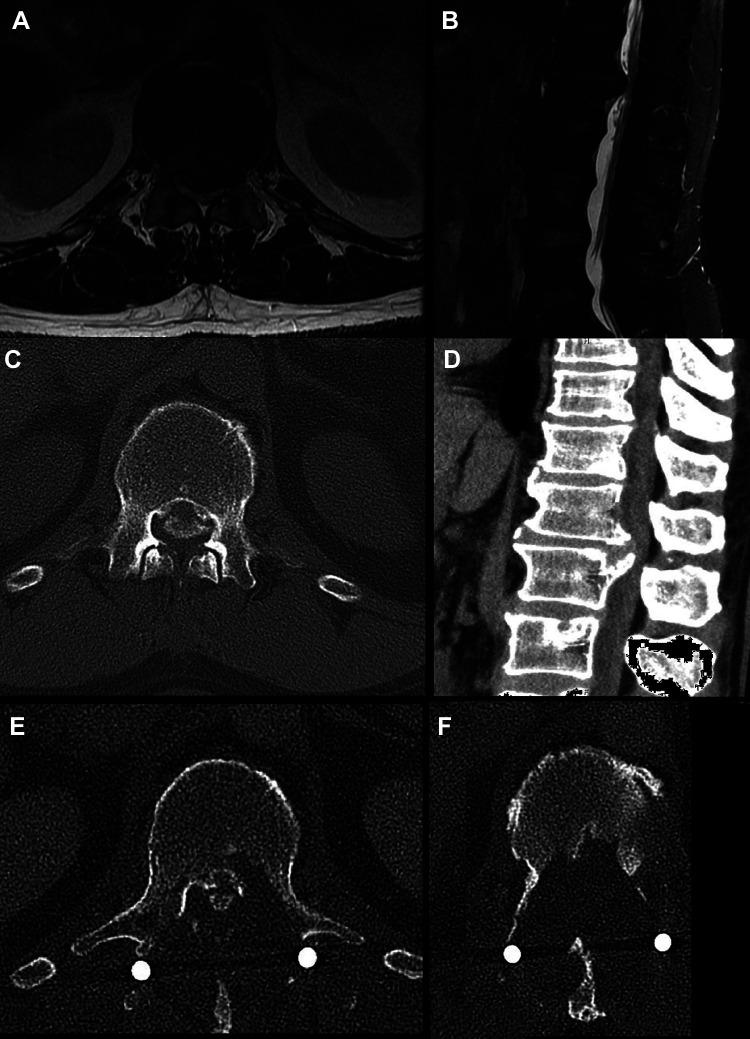

Posterior Minimally Invasive Transpedicular Approach for Giant Calcified Thoracic Disc Herniation.

Posterior surgery for thoracic disc herniation was associated with increased morbidity and mortality and new minimally invasive approaches have been recommended for soft disc herniation but not for calcified central disc. The objective of this study is to describe a posterolateral microscopic transpedicular approach for central thoracic disc herniation.

This is a single center retrospective review of all the cases of giant thoracic calcified disc herniation as defined by Hott et al. Presence of myelopathy, percentage of canal compromise, T2 hypersignal, ASIA score, and ambulatory status were recorded. This posterolateral technique using a tubular retractor was thoroughly described.

Eight patients were operated upon with a mean follow-up of 16 months. Mean canal compromise was 61%. Mean operative time was 228 minutes and mean operative bleeding was 250 mL. There were no cases of dural tear or neurologic degradation.

This is the first report of posterior minimally invasive transpedicular approach for giant calcified disc herniation. There were neither cases of neurological deterioration nor increased rate of dural tears. This technique is thus safe and could be recommended for treatment of this rare disease.